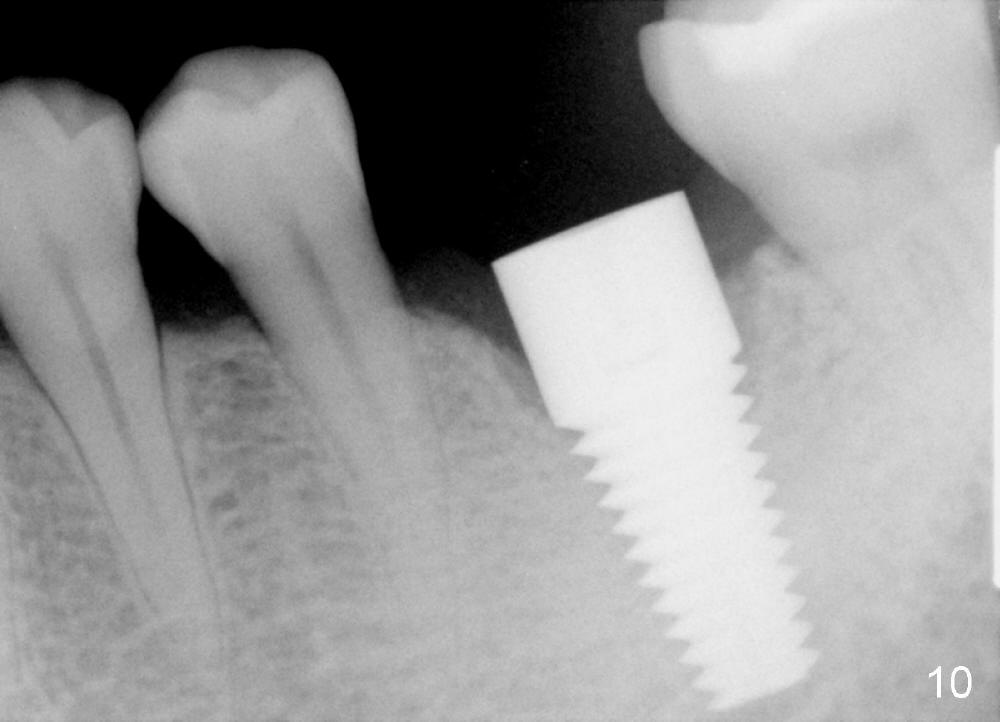

There is a thick gingival band buccal to the implant 7 months postop (Fig.9 *). Osteointegration occurs (Fig.10). The most unexpected finding is the formation of the papillae (Fig.11 *) when the permanent crown is seated. The cosmetic result is due to immediate placement of the large implant. Delayed implant usually cannot achieve this type of outcome.

Two and a half months post cementation, the buccal metal show is much less and confined to the midbuccal portion. It appears that the papillae increase their mesiodistal dimension (data not shown). Bone appears to remain stable over the implant surface 2.5 and 9 months post cementation (Fig.12 >,13). The papillae around the implant crown remain normal 11 months post cementation (Fig.14 *). No bone loss is noticed 26 (Fig.15) or 38 (Fig.16) months post cementation. There is no bone loss around the 7x17 mm tissue-level implant 6 years 8 months post cementation (Fig.17).